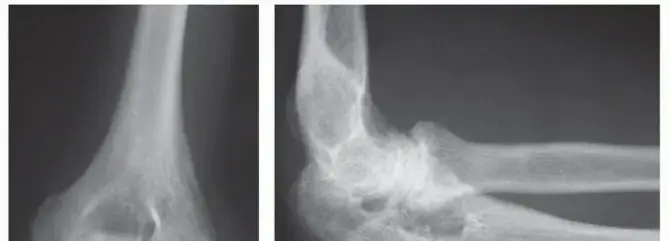

* الأشعة السينية (X-rays): للكشف عن أي تآكل في العظام أو تغيرات في المفصل.